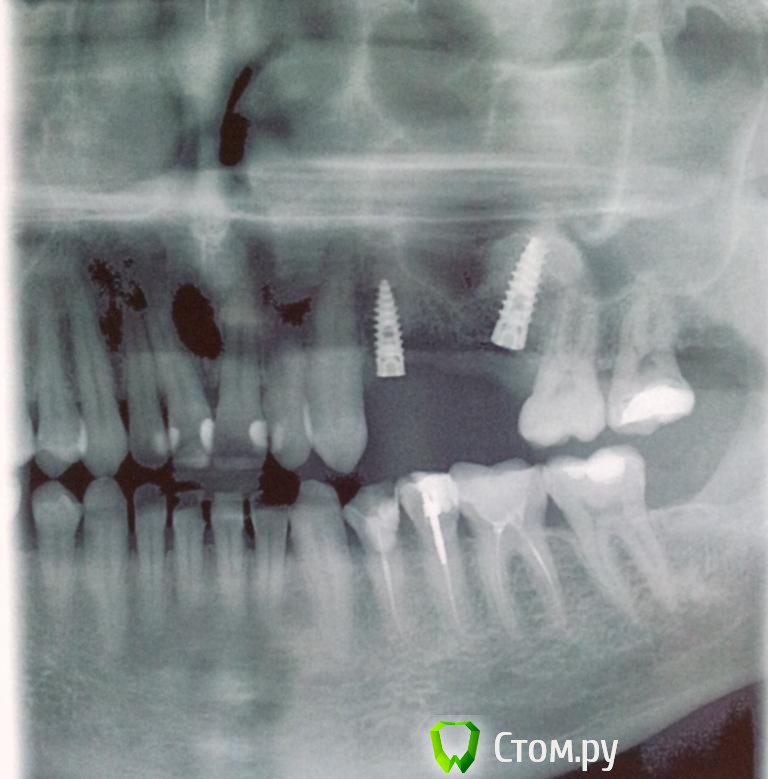

Пациент Ю Опубликовано 24 марта, 2014 Автор Поделиться Опубликовано 24 марта, 2014 Вот и удалили имплант. теперь три месяца ждём. А пока снимки что есть на руках. Виноватых не найти. Все по своему правы. Ссылка на комментарий

SDC Опубликовано 7 сентября, 2014 Поделиться Опубликовано 7 сентября, 2014 Вот и удалили имплант. теперь три месяца ждём. А пока снимки что есть на руках. Виноватых не найти. Все по своему правы.Ю, Вы хороший человек. Хочется пожелать Вам удачи и хорошего лечения.Пока есть время, займитесь антагонистами - велик риск их перелома, когда появятся коронки на имплантатах на в.ч. Ссылка на комментарий